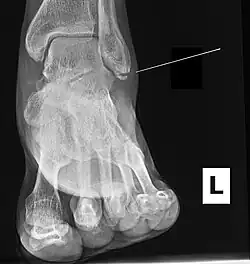

Ankle radiographs are used to detect widening of the tibiofibular syndesmosis or medial clear space. The medial clear space is the area between the talus of the ankle and the medial malleolus. Damage to the deltoid ligament and syndesmotic ligaments result in mortise instability, causing the talus to laterally shift and widen the medial clear space.[4][12] A clinical study, conducted in 2006 and published in the Journal of Bone and Joint Surgery, found that the medial clear space size of a normal ankle and an injured ankle measured at 4 millimetres and 5.4 millimetres in length respectively.[11] To confirm diagnosis, full-leg radiographs are used to inspect for fractures of the proximal fibula and widening of the interosseous clear space (or tibiofibular clear space). The interosseous clear space is the area between the medial side of the fibula and lateral side of the tibia. A peer-reviewed study, published in Injury in 2004, found that an interosseous clear space greater than 10 millimetres indicates diastasis of the syndesmotic ligaments.[4]